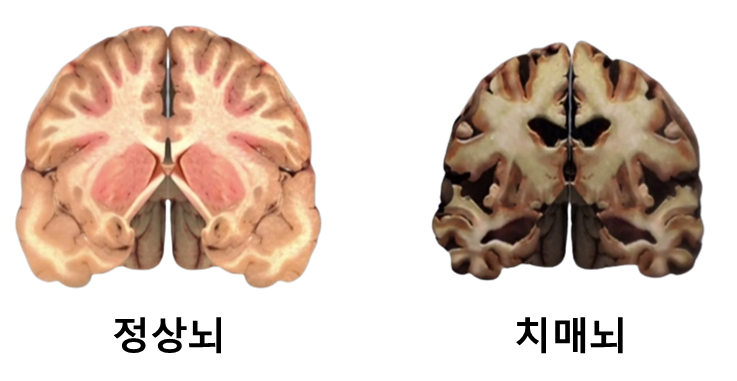

일반 노인성 치매보다 초로기 치매는 발병 후 뇌세포의 손상 속도가 빠르다는 것이 가장 큰 문제다.

치매에 노출되는 뇌를 살펴보면 독성물질인 뇌 조직 손상 단백질이 많이 발견된다.